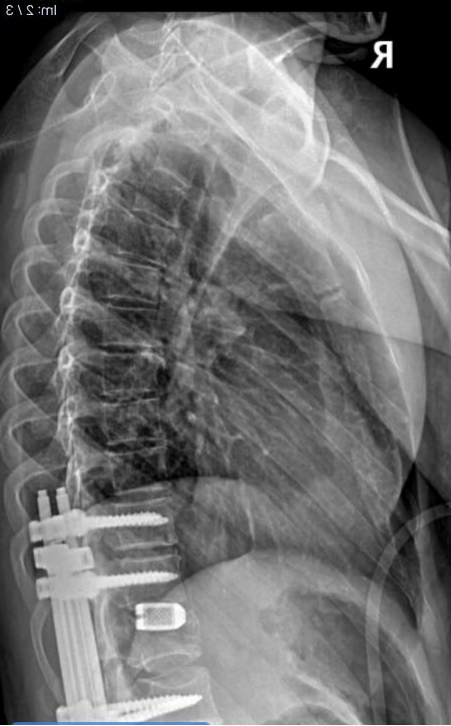

“医生说前6个月是康复黄金期,可我没钱治疗、没人久护,政府救助还得等一年,真撑不下去了……”安徽凤阳唐女士两个月前高空坠落,腰、胸骨等多处骨折,脊髓神经受损致下半身瘫痪,仅住院18天便因费用告急出院。如今她深陷“无人照料、政策梗阻、资金匮乏”三重绝境,一边是亟待把握的康复黄金期,一边是迫在眉睫的生存危机,迫切期盼社会爱心人士伸出援手筹集康复护理资金,更希望当地政府及残联特事特办,开启“绿色救助通道”为她留住生命希望。

唐女士术后护理需求迫切:每日两小时翻身防压疮,每月需专人陪同更换导尿管(忌颠簸、风寒),还需被动活动腿部防关节僵硬与肌肉萎缩,且伴有骨盆骨折,医生称本月底若恢复顺利,可尝试每天用轮椅活动20分钟,需拍片评估骨痂情况。其照料仅靠56岁的母亲,母亲身患头晕、单耳失聪、肢体疼痛等症,已多次因劳累想放弃,虽经家人劝说留下,却明确表示最多照顾到年底,一旦离开,唐女士将陷入无人照料的绝境。

近日,唐女士在家人陪同下赴合肥复查,医生叮嘱:“家人要有信心,别放弃,很多奇迹都会出现,关键要坚持康复训练,多活动关节。”这句话成了她的信念。她表示自己思路清晰,只要有照料、资金和政策帮扶,必全力配合治疗,哪怕仅能生活自理,也不想躺床成累赘,想陪伴女儿长大。目前她仍以卧床为主,本月底需拍片评估骨痂情况,达标后可每天用轮椅活动20分钟。